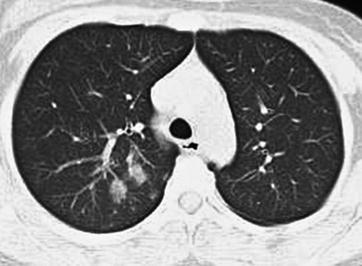

CT Scanning

CT scanning demonstrates pulmonary consolidation, thickened bronchial vascular bundles, ground-glass opacity, lesions at the lobular center, and nodular shadows (Figs. 23.18 and 23.19). In rare cases, cords like shadow can be demonstrated, with accompanying pleural effusion.

Adult measles complicated by pneumonia. At day 2 after hospitalization, CT scanning demonstrates ground-glass opacity in the apical posterior segment of the left upper lung lobe